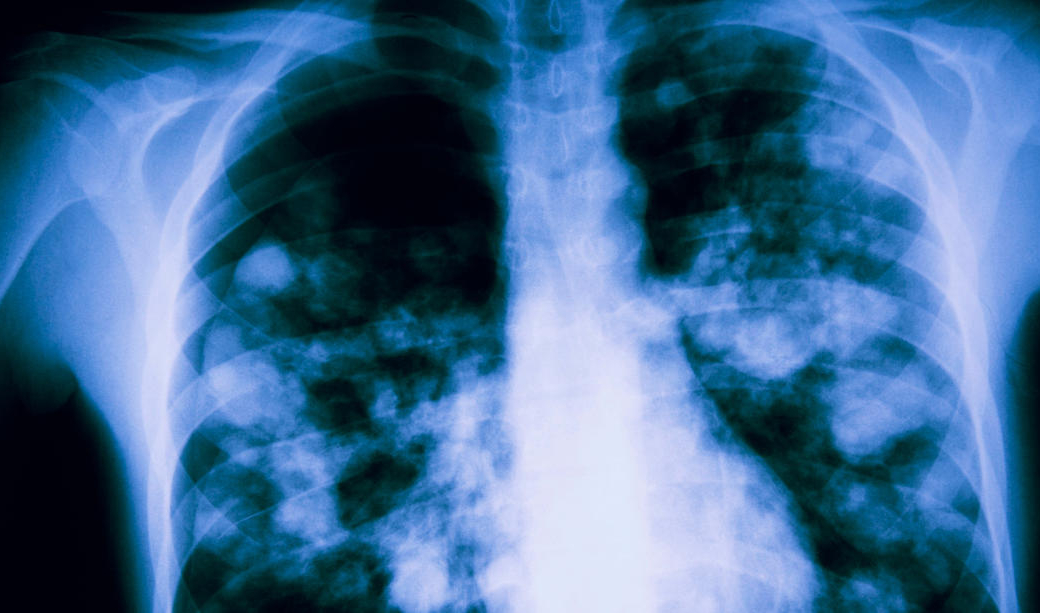

4) Le diagnostic clinique est évoqué devant une pneumopathie, notamment si elle est associée à des douleurs musculaires, des lésions dermatologiques et une cytolyse hépatique, tout particulièrement en présence de cas groupés en collectivité. Une radiographie ou un scanner thoracique peut être demandé en fonction de la gravité des symptômes. Une confirmation du diagnostic d’infection à Mycoplasma pneumoniae se fait, si besoin, en milieu hospitalier, par PCR (polymerase chain reaction ) sur prélèvement respiratoire, pharyngé ou nasopharyngé et/ou par diagnostic sérologique.